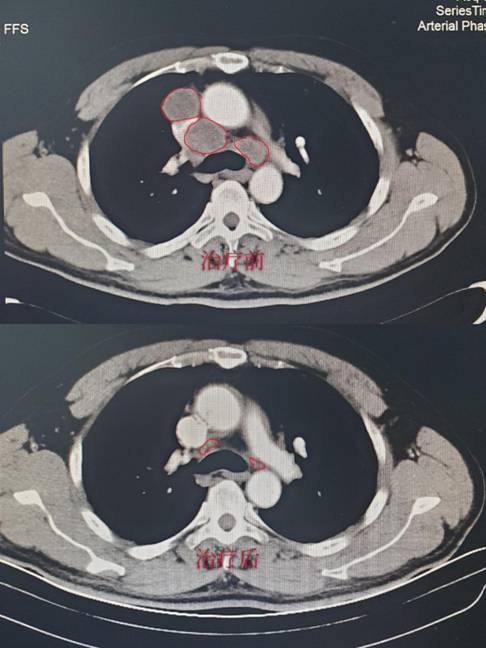

病例1:储某某,诊断为:左肺小细胞癌广泛期。经2周期治疗后复查胸部CT,肿瘤缩小达90%,肿瘤接近消失,达到很好的效果;(CT结果如下,红色线框内为肿瘤组织。)